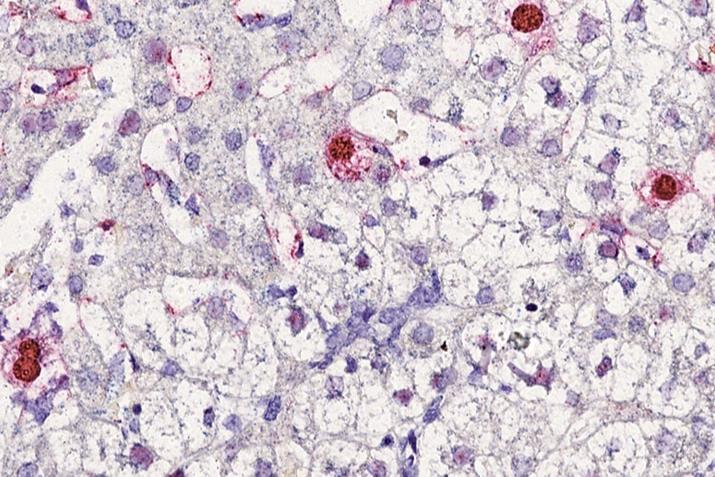

Pesquisadores da Universidade Federal do Rio Grande do Norte (UFRN) alcançaram um marco significativo na área de virologia ao identificar potenciais regiões antigênicas e imunogênicas de um novo vírus humano. Nomeado circovírus humano tipo 1 (HCirV-1), o circovírus, pequenos vírus de DNA de fita simples, normalmente encontrado em animais, foi inicialmente detectado em uma paciente transplantada de coração e pulmão que procurou tratamento para hepatite crônica na França. A descoberta, resultado de uma colaboração com cientistas internacionais, foi publicada no International Journal of Surgery (JIF 12.5).

Os resultados revelaram 138 mutações no gene do capsídeo viral, estrutura fundamental para que o vírus consiga infectar células e se multiplicar. Para Jonas Ivan, essa constatação traz um alerta para a saúde pública, sobretudo em relação a pacientes imunossuprimidos ou com doenças hepáticas, que podem estar mais suscetíveis a esse tipo de infecção.